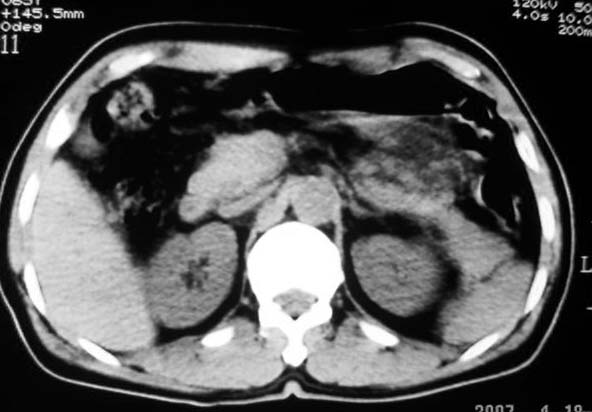

定位:病灶位于胃腔外,大弯侧后下方.

特征:实质性肿物,边界清楚,内见低密度影,明显压迫胃壁,并形成切迹.

考虑:脾门淋巴瘤或间质瘤.

胃大弯侧,胃底与胃体交界处可见一圆形软组织肿块影,边缘较光整,内部密度较均匀

考虑:脾门淋巴瘤或间质瘤

考虑:胃间质瘤?息肉?

病灶起源于胃壁向腔内外突出,边缘光整,内可见片状低密度区,考虑胃壁非上皮性肿瘤可能性大

病灶起源于胃壁向腔内外突出,边缘光整,内可见片状低密度区,考虑间质瘤可能性大,建议增强扫描。